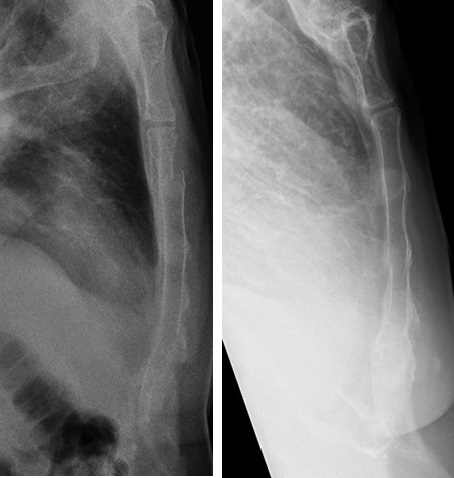

Image radiologique de

fracture de côte 4th , 5,6,7,8th droit du thorax .

Pneumothorax du poumon droit . Cliche de face PA

pulmonaire |

Même cas en OAD , les

fractures à diplacement angulaire et de glissement

être en vue très nette . |